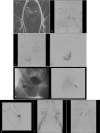

Arteriovenous malformations (AVMs) are high-flow vascular anomalies that have demonstrated a very high recurrence rate after endovascular treatment, surgical treatment, or a combination of both. Surgical treatments have shown good response when they are small and well localized but a poor response when diffuse. A better understanding of the nature of the lesion has led to a better response rate and a safer treatment for these patients. This has been accomplished through a detailed understanding of the angioarchitecture of the lesion, enabling a tailored approach in reaching and targeting the nidus of the AVM with different liquid embolic agents, more specifically ethanol. Flow reduction techniques help in exposing the nidus to sclerosant agents. A clinical classification, the Schobinger classification, will help determine the appropriate time to start or to pursue therapy.